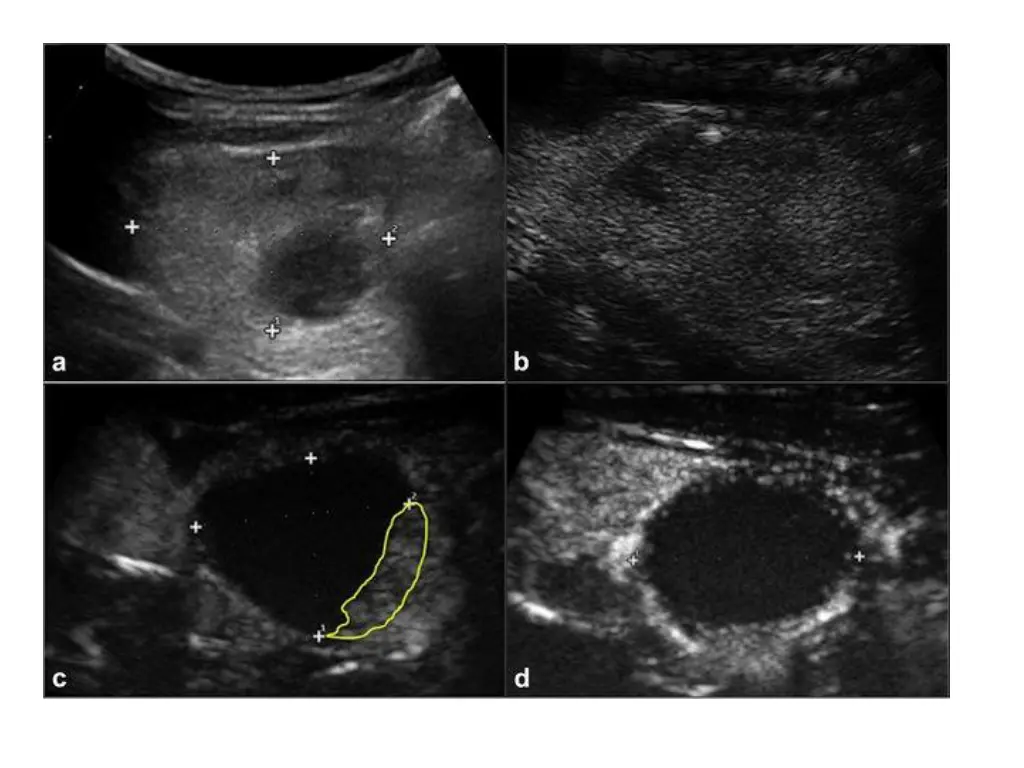

Techniques: Before starting ablation, the target tumor is divided into multiple conceptual ablation units, and RFA is performed in a unit-by-unit manner by moving the electrode tip. The use of local anaesthesia rather than general anaesthesia or sedation. If a metastatic tumour exists adjacent to these nerves, the hydrodissection technique is useful to prevent thermal injury.

Ablation should be terminated when all conceptual units have changed to transient hyper echoic zones. RFA is usually performed on both the tumor and the surrounding normal tissue in order to prevent local recurrence.

Treatment efficacy: Volume reduction , therapeutic success rate (volume reduction >50%) , complete disappearance of the treated cancer, serum thyroglobulin concentration, cancer perfusion, and changes in echogenicity. Ethanol and thermal ablation for malignant So Yeong Jeong, Jung Hwan Baek, Young Jun Choi & Jeong Hyun Lee International Journal of Hyperthermia 2017

Results of Ablation: The mean FU duration after ablation ranged from 7.8 months to over 53 months. The mean size of the index tumor before and immediately after ablation and at last FU ranged from 4.3 to 7.5 mm (41 to 157 mm3), 11.8 to 14.1 mm (517.6 to 3099.4 mm3), and 0 to 4mm (0 to 70 mm3), respectively.

Disappearance rate was defined as complete tumor disappearance or the presence of residual scar like changes.